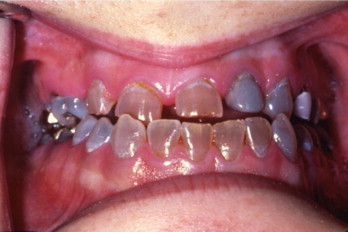

Pt sits down in chair and presents with these teeth. Eyes are blue and legs are bowed. What are you thinking they might have?

osteogenesis imperfecta